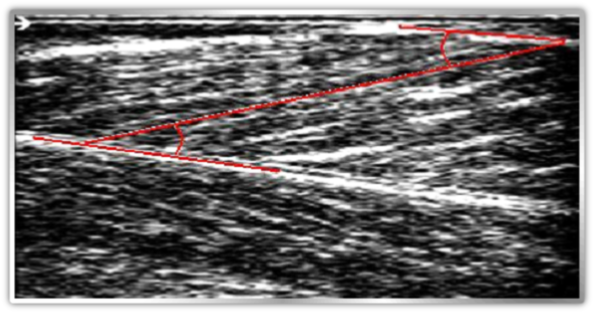

Six healthy subjects, three male and three female volunteered to participate in the study. Average (mean, +/-SD), age 31+/- 1.67 years, height171+/-8cm, body mass 77+/- 12kg . Participants walked and run on a treadmill at speeds of 4.5 and 7.5km/h, respectively. Six retroreflective landmarks were placed over the base of fifth metatarsal, lateral malleolus, posterior aspect of calcaneum, head of fibula, lateral femoral condyle and greater trochanter. All landmarks were on right side. 3D motion analysis took place using CODA system (Charnwood Dynamics). Light Emitting Diodes were attached to body landmarks and their 3D position was determined by precalibrated cameras. A PC based ultrasound system (Echoblaster 128, Vilnius LT-) was used, with flat probes which attached to the segments at middle ,proximal and distal part of the muscle belly. The vertical velocity of the calcaneal marker was used to determine when the foot contacted the ground.

Muscle fibre length and orientation were made at 0, 20, 40, 60, 80 and 100% of both stance and swing phase. The length of the fascicles was measured as length of the echo that runs diagonally from superficial to deep aponeurosis along the fascicle.